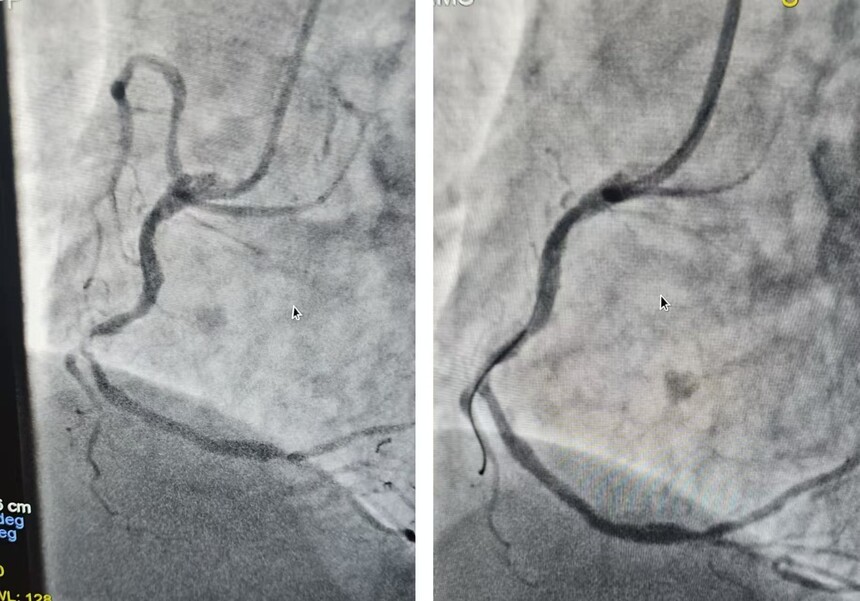

无缝衔接:绿色通道上的“生命竞速” 22:20,载着患者的敦寨镇中心卫生院救护车鸣笛出发。救护车上,随车医生持续监测生命体征,并通过5G设备实时传输心电图。县人民医院同步启动导管室,心内科、急诊科、麻醉科、介入室等多学科专家团队严阵以待。 22:45,患者直达导管室,造影显示右冠中段次全闭塞,狭窄99%,团队在30分钟内成功行右冠介入治疗,D2B时间(入院至球囊扩张)仅26分钟,较国际标准90分钟缩短70%。 “从患者进院到导管室就位,我们打破了常规流程的壁垒。”实施手术的县人民医院心内科主任龙兴强介绍,多学科团队通过预置方案实现无缝衔接,最终在“黄金救治时间窗”内完成冠状动脉介入手术,术后患者胸痛即刻缓解。